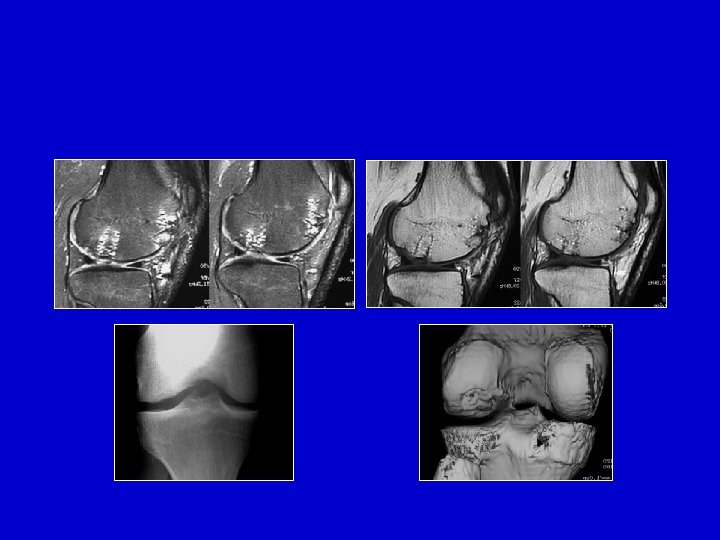

Radio RMN

L’osteocondrite é ferma Importanza della visione diretta per verificare lo stato della cartilagine: artroscopia o artotomia e RMN o TAC

Proiezione rx-grafica della gola intercondilica L’osteocondrite é ferma , uno scalino é visibile sotto la cartilagine

Osteocondrite aperta , il frammento è ancora in posizione